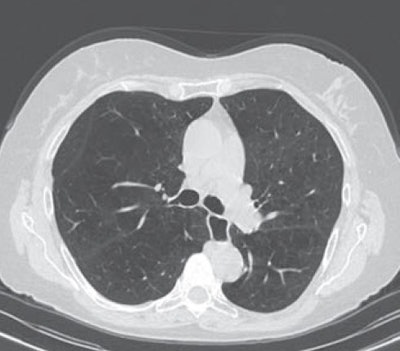

A 65-year-old man with severe lung emphysema (light blue on images below) seen on axial CT image (image 1 above), CT image including AI-based calculation (image 2), and 3D model (image 3). Extent of low-attenuation volume is seen inside green outline in both lungs in image 2. Purple outline in anterior right part of image 2 marks boundary between upper and middle lobes. Gray outline in image 2 correctly segments lower part of upper lobe and ensures that all lung tissue was considered. Also in image 2, orange outline denotes margin of tracheobronchial tree, and blue outline denotes margin of left lower lobe. All images courtesy of the AJR.The results indicate that AI-based emphysema quantification meaningfully reflects clinical pulmonary physiology, according to the researchers.